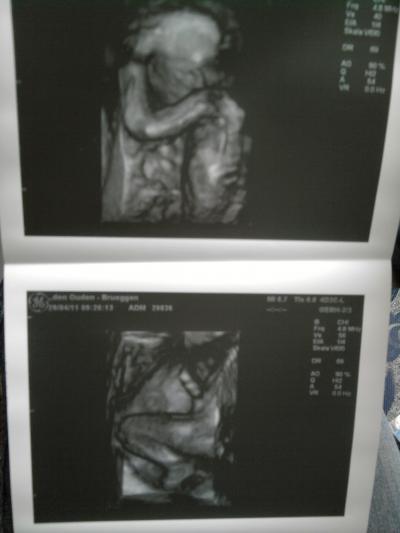

hier einmal die bilder von heute =) mit dem denker der knapp ne halbe std seine hand nicht vom kopf weg nehmen wollte hihi und das untere eins seiner beine + halben po und nabelschnur..